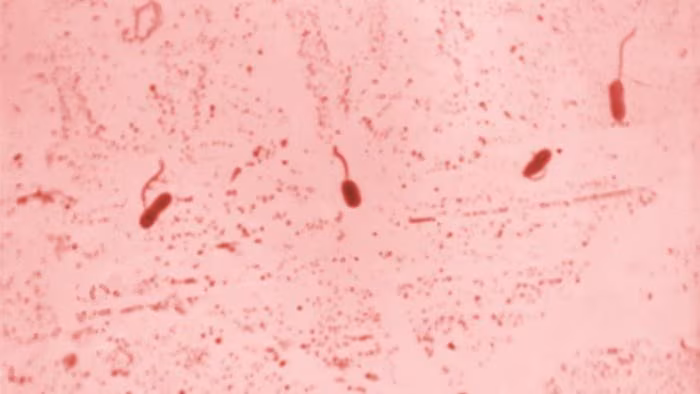

- Learn about Vibrio and vibriosis, the illness caused by infection with some kinds of Vibrio.